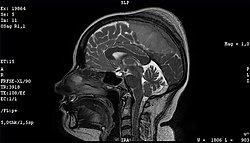

Retroviral replicating vectors

A brainstem glioma in four-year-old. MRI, sagittal, without contrast

Led by Prof. Nori Kasahara, researchers from USC, who are now at UCLA, reported in 2001 the first successful example of applying the use of retroviral replicating vectors towards transducing cell lines derived from solid tumors.[112] Building on this initial work, the researchers applied the technology to in vivo models of cancer and in 2005 reported a long-term survival benefit in an experimental brain tumor animal model.[113][unreliable medical source?] Subsequently, in preparation for human clinical trials, this technology was further developed by Tocagen (a pharmaceutical company primarily focused on brain cancer treatments) as a combination treatment (Toca 511 & Toca FC). This has been under investigation since 2010 in a Phase I/II clinical trial for the potential treatment of recurrent high-grade glioma including glioblastoma and anaplastic astrocytoma. No results have yet been published.[114]